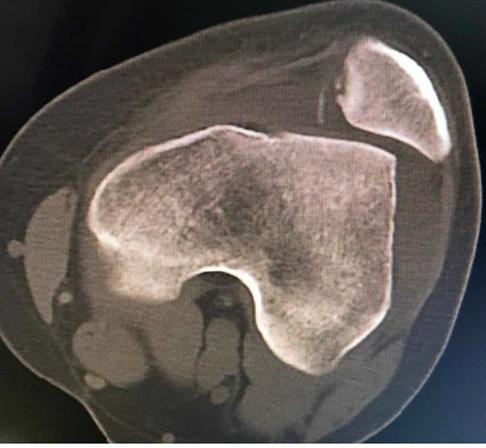

膝关节CT